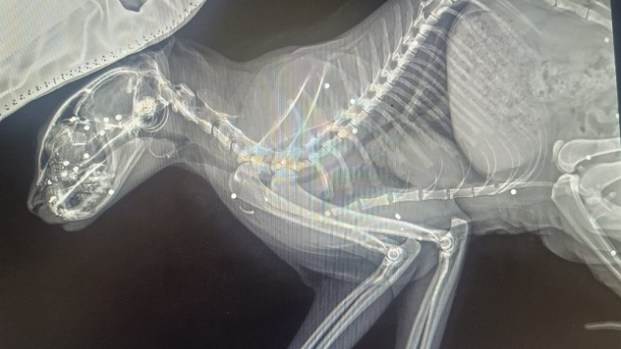

La proprietaria lo ha portato immediatamente dalla veterinaria di Città di Castello Beatrice Borrani, che ha diagnosticato ferite gravissime: Leo era stato colpito con una fucilata in pieno volto. Dalle radiografie è emerso che il piccoletto sarebbe stato colpito mirando di proposito alla testa – un solo colpo assolutamente non accidentale – che ha lasciato numerosi pallini di piombo conficcati nel cranio ma anche nel corpo.

Il gatto ha perso completamente la vista da un occhio, mentre dall’altro resta solo una debole speranza di recupero parziale, una volta guarito l’edema cerebrale. Ora è accudito con amore e cure costanti, ma le conseguenze di quei proiettili nel corpo restano incerte.